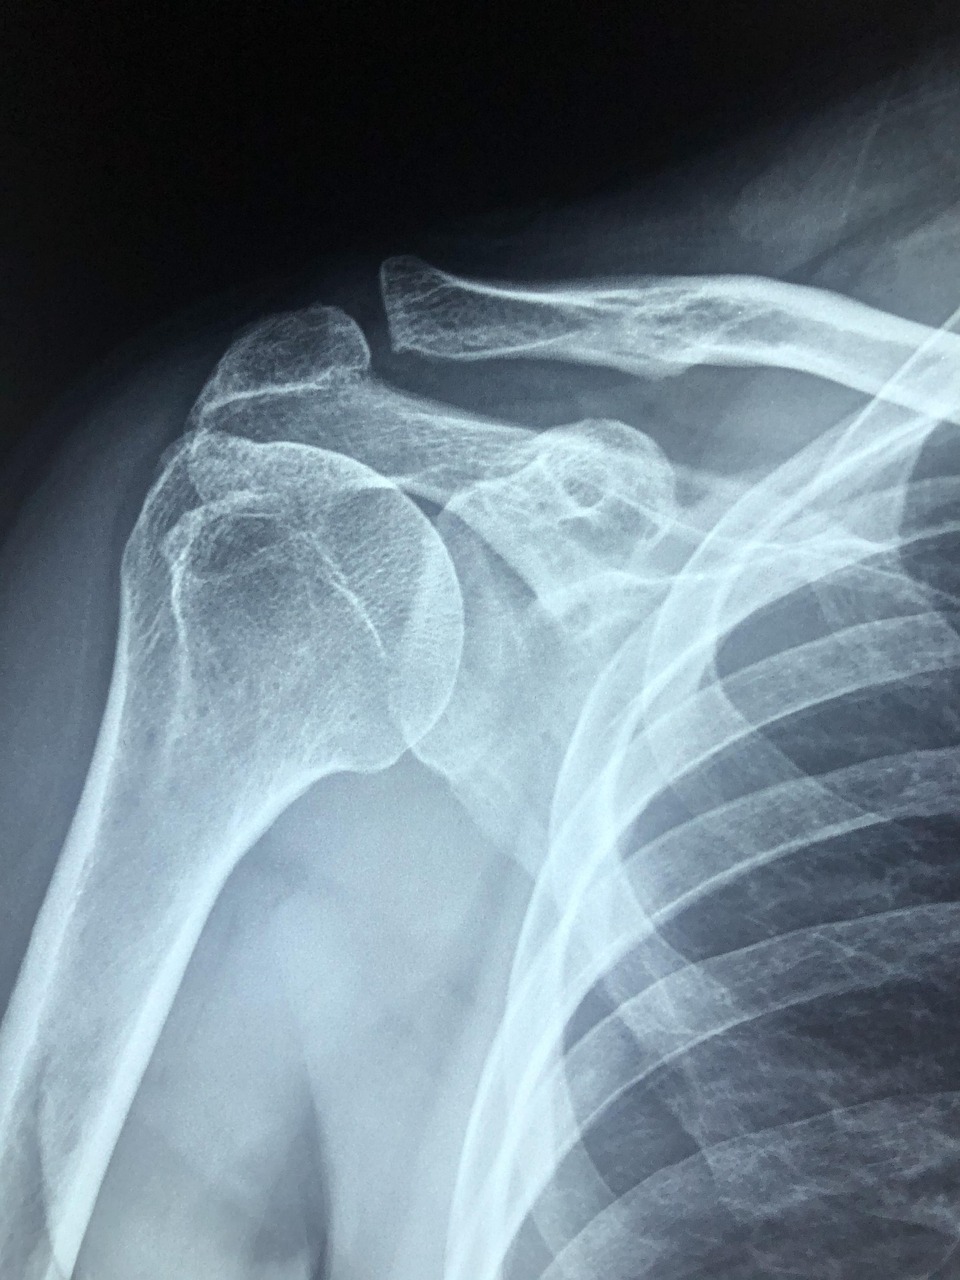

X-ray, MRI, 초음파 검사: 회전근개 손상 여부나 염증 유무를 확인